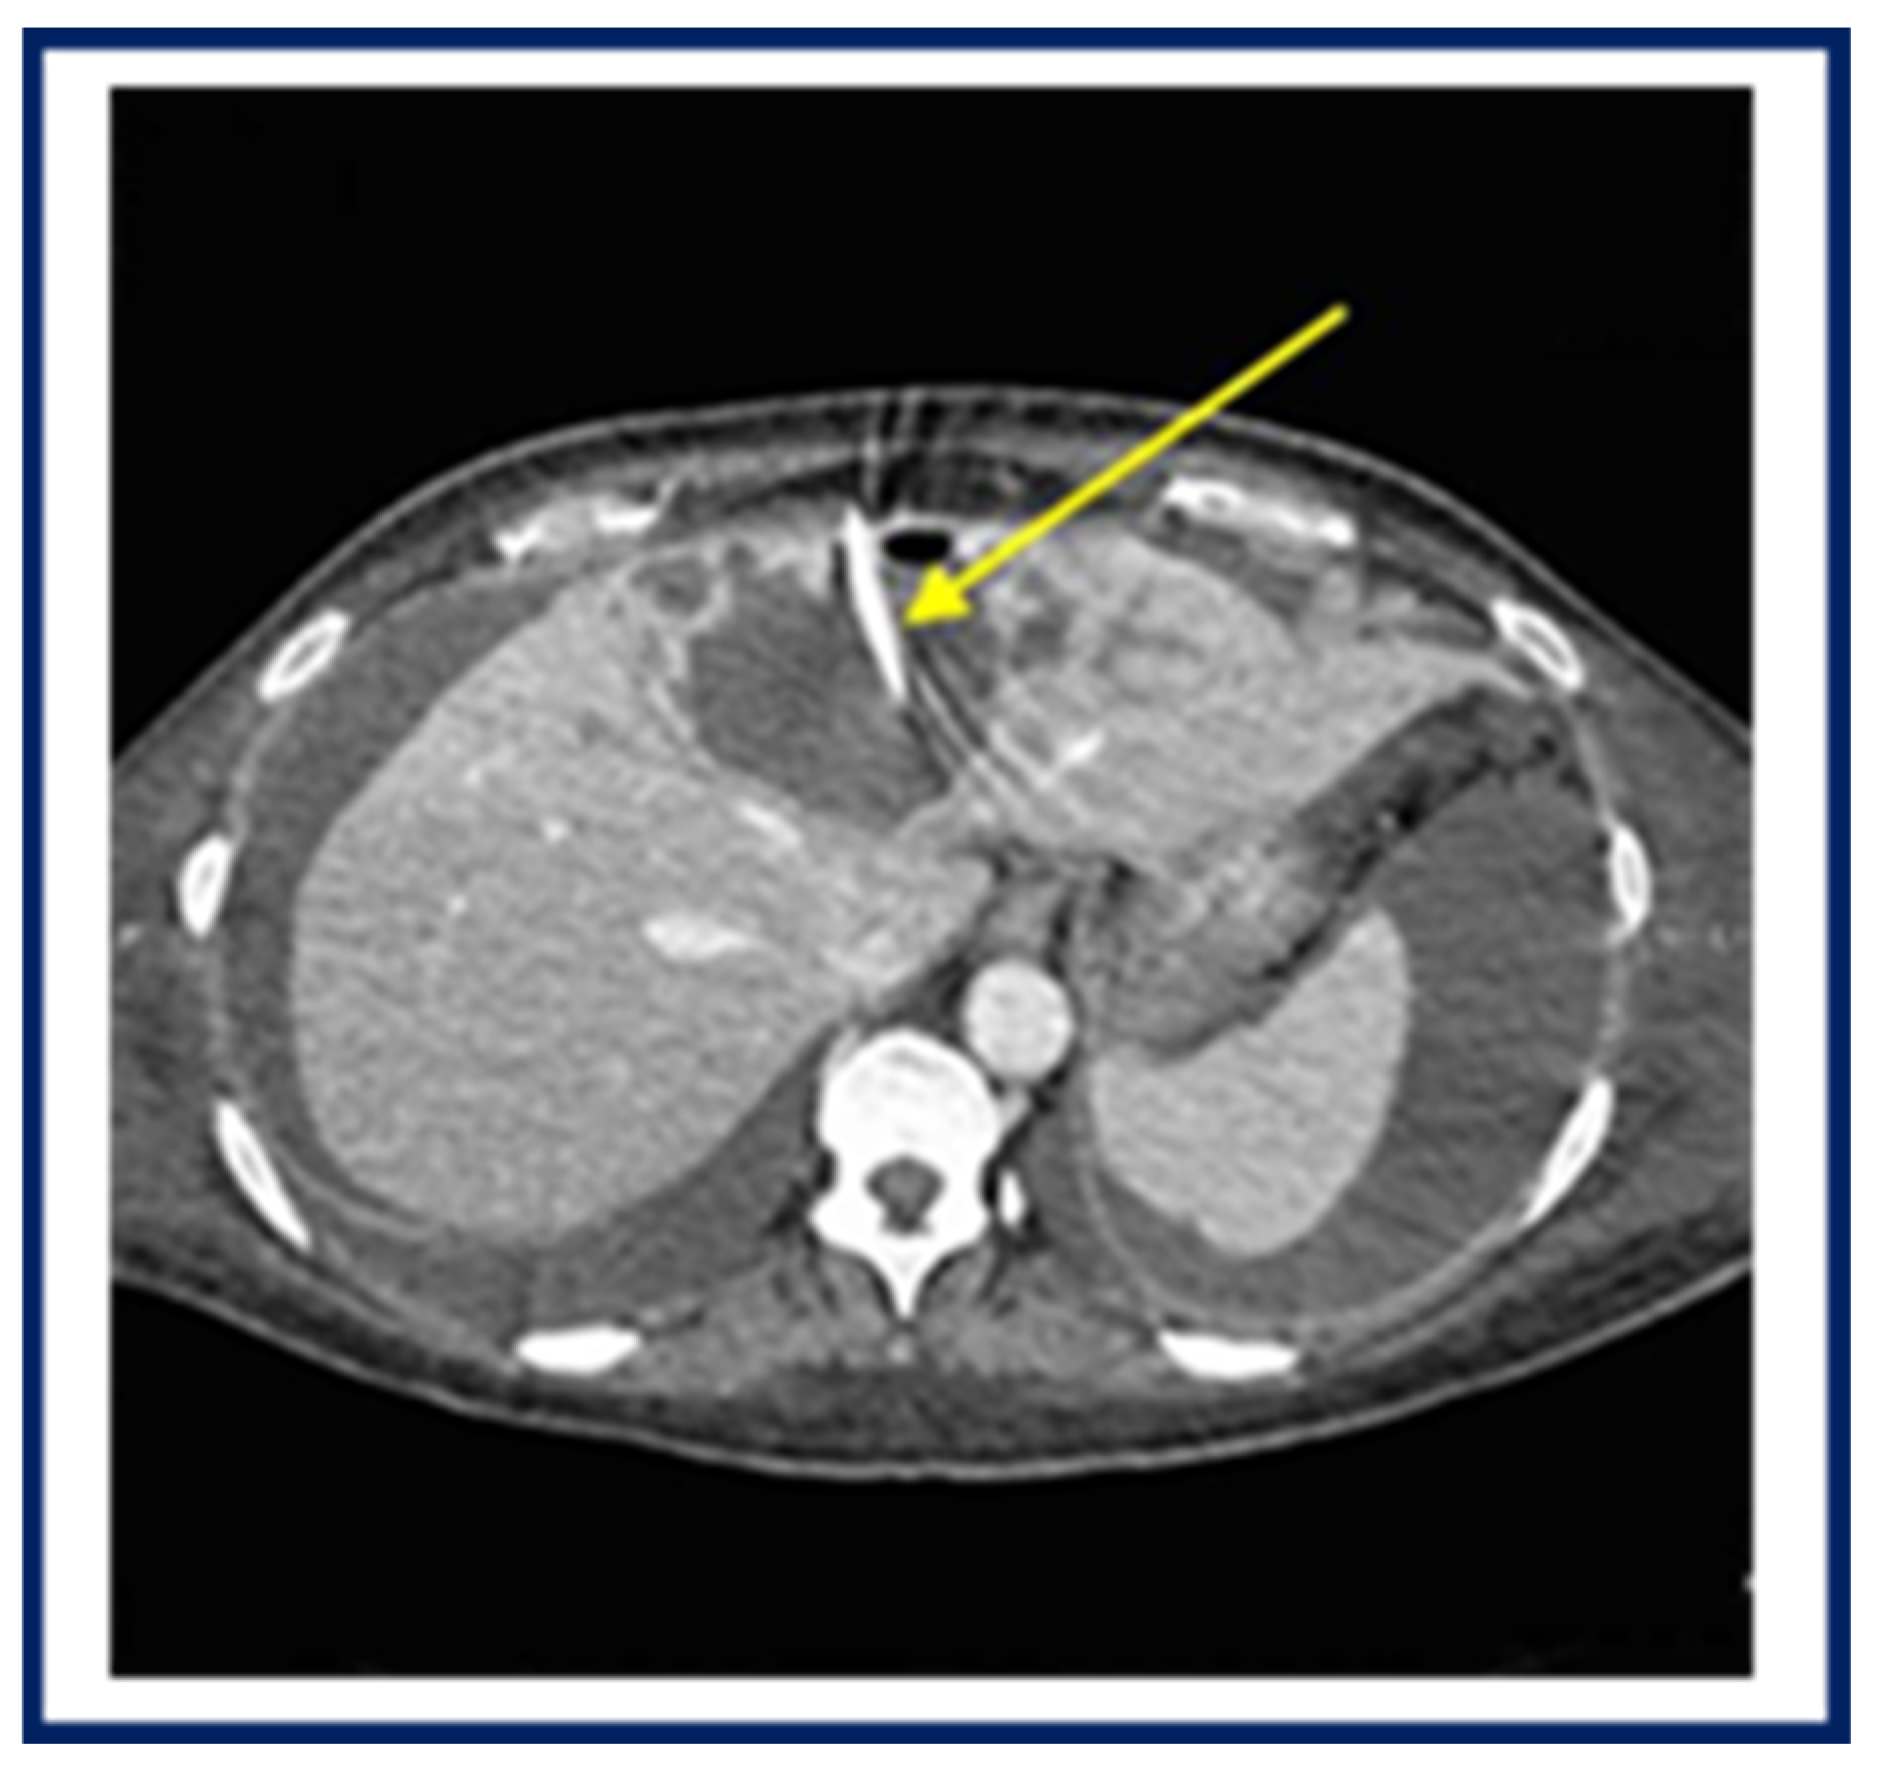

2. Case Report 1

3. Case Report 2

4. Case Report 3